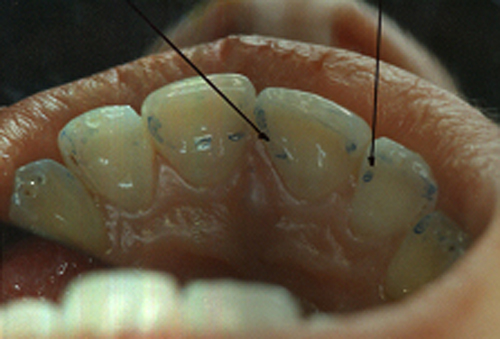

En ciertas áreas del saber humano, el lenguaje confuso o criptográfico Muchas son las técnicas elaboradas para lograr un desgaste selectivo, y numerosos autores han expuesto en su momento variadas formas de lograr una función oclusal fisiológica mediante el ajuste de la misma. Han pasado años desde entonces y, sin embargo, aún hoy, un altísimo porcentaje de profesionales “navega” por el mar de la confusión oclusal, dada la diversidad de conceptos y escuelas, sin lograr arribar a costa alguna donde poder anclar un conocimiento sólido sobre cómo tratar la oclusión Ya se esté realizando una simple obturación, endodoncia, incrustación, radectomía u ortodoncia, la lógica pocas veces, en la mayoría de los casos, vincula un tratamiento con otro, siendo el resultado final el mismo caos inicial; enmascarado por mucho tratamiento profesional. El ajuste oclusal es un medio inicial de proveer al sistema enfermo de: Dicha técnica, que puede ser terapéutica en sí misma; consta de dos etapas, a saber: 1) Ajuste Oclusal por Adición Mediante el estudio de la guía anterior, encargada de efectuar las Disclusiones durante las excursiones mandibulares, podremos observar si ésta es funcional o no. • Marcas de carácter continuo, si en ese recorrido se produce la Disclusión de los sectores posteriores y todo marcha correctamente. FIG 1-2 Si por el contrario observamos: • Marcas de carácter discontinuo, significa que dicha Disclusión se está efectuando por medio de una pieza dentaria posterior a la guía anterior. FIG 3-4-5 (FIGS. 3, 4 Y 5). En la figura 6 las flechas indican, en un caso clínico de análisis oclusal, la presencia de marcas discontinuas que indican Interferencias en Propulsiva. FIG 6-7 Y por último, si existieran: • Abrasiones de las áreas discluyentes en las áreas de diagnóstico de la guía anterior, deberemos aportar material a dicha zona para no permitir el choque lateral de las piezas posteriores (Ajuste Oclusal por Adición) En las imágenes 11 y 12 podemos observar la adición de composite en la punta de un canino derecho, previa la observación de la Faceta Parafuncional remarcada durante el análisis oclusal en el articulador. (FIGS. 8 A 12). 2) Ajuste oclusal por Sustracción o Desgaste Habiendo cumplido ya con la verificación de la funcionalidad de la Guía Anterior, comenzamos los desgastes en céntrica, a fin de lograr un único arco de cierre, guiado eficazmente por la Guía Anterior; es decir: la coincidencia entre Oclusión Habitual y Oclusión en Relación Céntrica. En este caso, intentar gastar dichos puntos, de ser posible sólo en las cúspides de corte o no fundamentales: • Crestas Triangulares Internas, Cúspides Vestíbulares Superiores • y un poco de las Crestas Triangulares Internas, Cúspides (FIGS. 13 A 16). Si la deflección es hacia el lado opuesto, se invierten los desgastes. En las migraciones hacia adelante, las únicas razones posibles están en los puntos estabilizadores (FIG. 17); es decir: -Vertientes Distales de los Rebordes Marginales, Triangulares (FIG 17) (FIG 18 A-B-C-D) Obsérvese cómo, en una boca prácticamente entera, comienzan a “desmoronarse” prismas adamantinos (FIG. 19), como consecuencia de un punto prematuro de contacto, ubicado en la posición de un estabilizador, que provoca la discrepancia horizontal postero-anterior causante de dicho efecto (FIG. 20). FIG 19-20 Dicho punto, será necesario ajustarlo antes de cualquier tratamiento en la zona ¿Cuáles serían las consecuencias si esos incisivos fueran implantados tal como es frecuente observar en múltiples congresos y cursos de implantología, donde el tema de la oclusión no es más que un cuadro polifacético y anecdótico? 14 15 16 17 Todo producto del adelantamiento mandibular Realizados ya los desgastes en céntrica, obteniendo de esta manera un único arco de cierre, es decir, oclusión en relación céntrica, debemos realizar el ajuste de las excéntricas, apoyando la acción de la guía anterior, para lo FIG 22 a. De un lado a otro de un mismo maxilar, la imagen es especular, o sea invertida. b. En hemimaxilares cruzados, la imagen es idéntica. Allí donde existan colisiones entre cúspides, se deberá crear un surco para que dicha cúspide antagonista migre a su través, tanto en el lado de no trabajo, como en el de trabajo y en el de propulsión. FIG 23 Es importante conservar esta parte del surco, ya que si no existieran, los contactos entre cúspides serían en superficie y no puntiformes (fig. 24). FIG 24 1. Obtener un único arco de cierre con coincidencia entre oclusión habitual y relación céntrica. 2. El cierre mandibular debe ser recibido sólo por la tabla premolar-molar. 3. Durante las excursiones funcionales es la guía anterior la que debe sufrir las fuerzas laterales. 4. De cumplirse estas dos premisas debemos obtener libertad de desplazamiento (no confundir con libertad en céntrica) a las piezas posteriores mediante la creación de surcos disclusivos. Examinadas ya las posibles migraciones mandibulares y los desgastes o aposiciones necesarios para poder ocluir en céntrica, es fundamental recordar que, previamente a todo tipo de ajuste, se ha hecho necesario ubicar a la mandíbula en relación céntrica. Para ello debemos utilizar el propio funcionalismo muscular 22 FIG 25 Y esto no significa otra cosa que: piezas dentarias estables en todos los planos del espacio, ATM centrada en la cavidad glenoidea, periodontos sin tensión, músculos en la dimensión de elongación adecuada para un fisiologismo Paz absoluta en la intimidad del Sistema Estomatognático. Y así, como corolario final, es posible establecer una regla de oro similar en importancia a la conocida formula: Forma = Función Ésta es: FIG 26 FUNDAMENTOS NEUROFISIOLÓGICOS DEL REGISTRO DE OCLUSIÓN EN RELACIÓN CÉNTRICA ( ORC) MEDIANTE EL USO DE LAMINILLAS DE LONG CUADRO

En el transcurso de dichas Lateralidades o Propulsiva, podremos ver:

(FIG. 1-2)